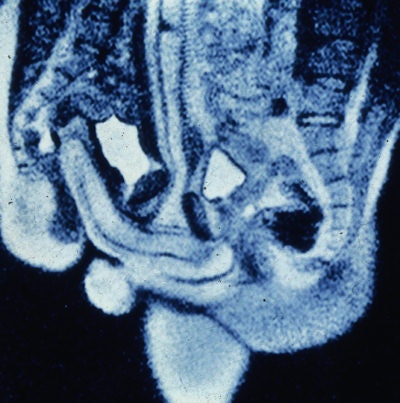

"The first scan was so iconoclastic, so different from the da Vinci drawing, that immediately I knew it had moved from being an explorative study to a scientific study," he said. "It cut new ground in terms of anatomy, physiology, and imaging technique."

In effect, the MR images of the female sexual response and the male and female genitals during coitus are feasible and beautiful, van Andel continued, "and the penis during intercourse in the missionary position has the shape of a boomerang and not of an S as shown by Dickinson."

Van Andel explained that the images obtained drew interesting comparisons to the hypothesized anatomy of human coitus, as drawn by da Vinci and Dickinson.

"The caudal position of the male pelvis during intercourse, the potential size of the bulb of the corpus spongiosum, and the capacity of the penis in erection to make an angle of around 120° to the root of the penis, enabled penetration along the bottom of the symphysis up to the woman's promontorium," they wrote. "The 'hidden' position of the root of the penis must have been the reason for the difference between the angle of penetration as envisaged by Dickinson and the penetration angle on our images."

During missionary position intercourse, the penis is not straight, as drawn by da Vinci, Van Andel added.

"The penis has a hanging part that gets twice as thick and long, but internally there is a part that is as long and thick, and this part is as important as the external part," he said. "This is different to the da Vinci image, but we see this with ours. Da Vinci drew this five centuries ago, and nobody had ever checked the truth of it."